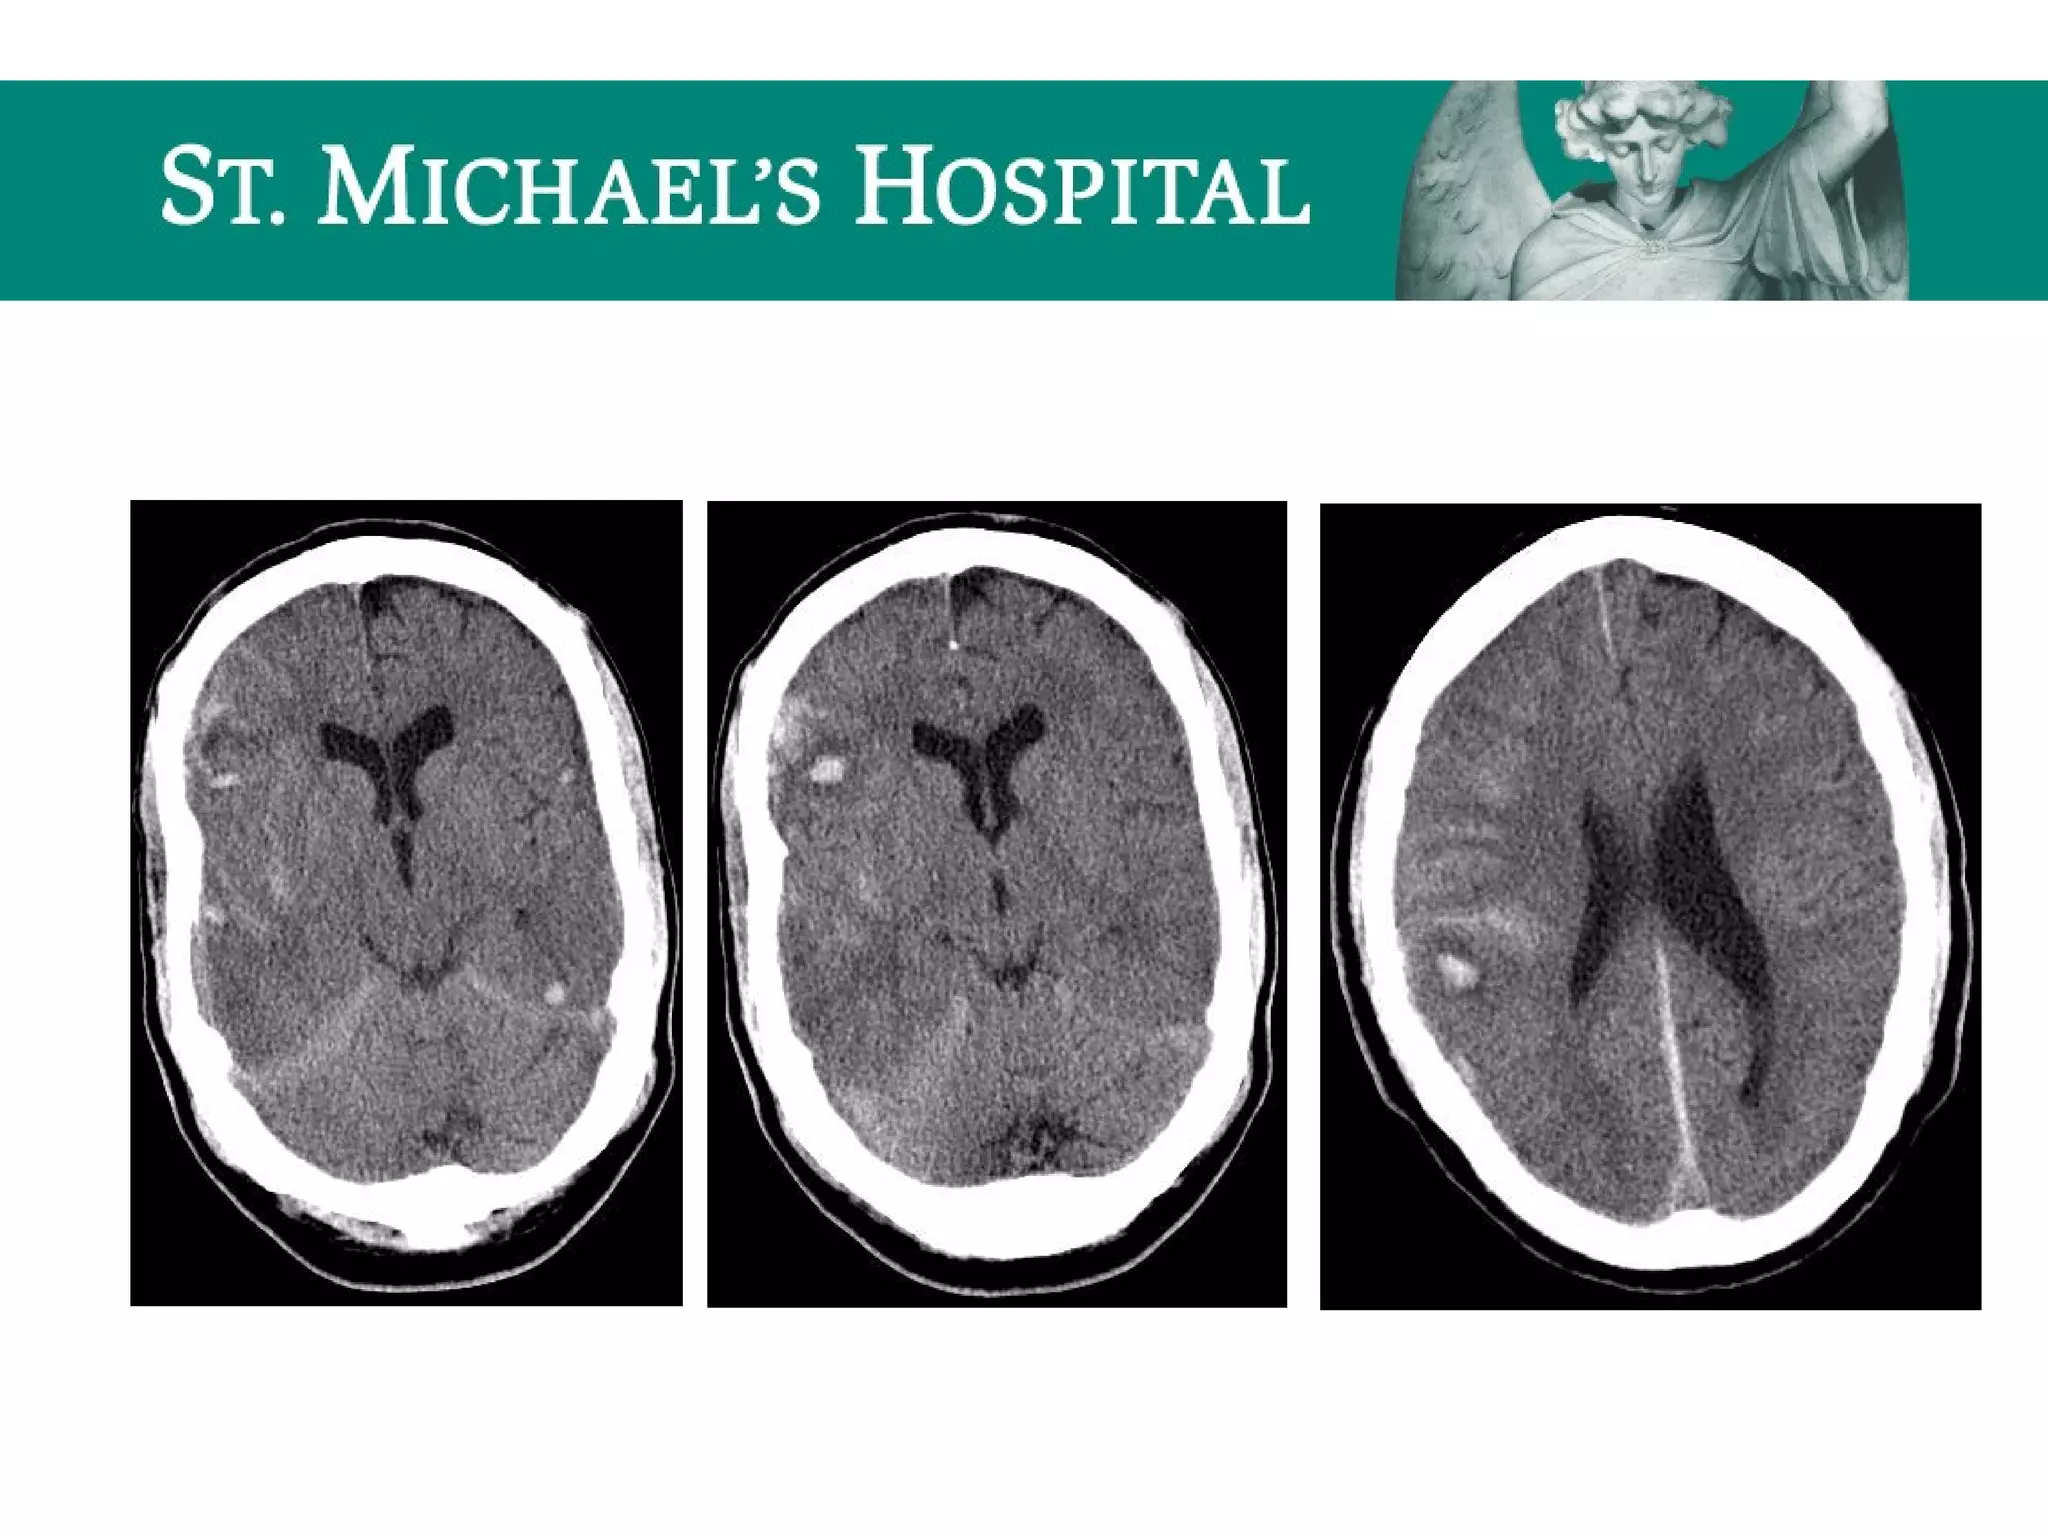

Diffuse Axonal Injury (DAI)

 Shear injury – secondary to severe rotational acceleration and

deceleration forces on the brain

 Unenhanced CT:

 Often normal (50-80%)

 Small hypodense foci due to traumatic edema

 Hyperdense petechial hemorrhages at the corticomedullary junction (20-50%)

 10-20% evolve to focal mass lesion (hemorrhage/edema)

 New lesions may become apparent on delayed scans

 Note: T2 GRE MR sequences are the most sensitive and demonstrate

hypointense foci at characteristic locations; microbleeds may only be

visible on GRE.